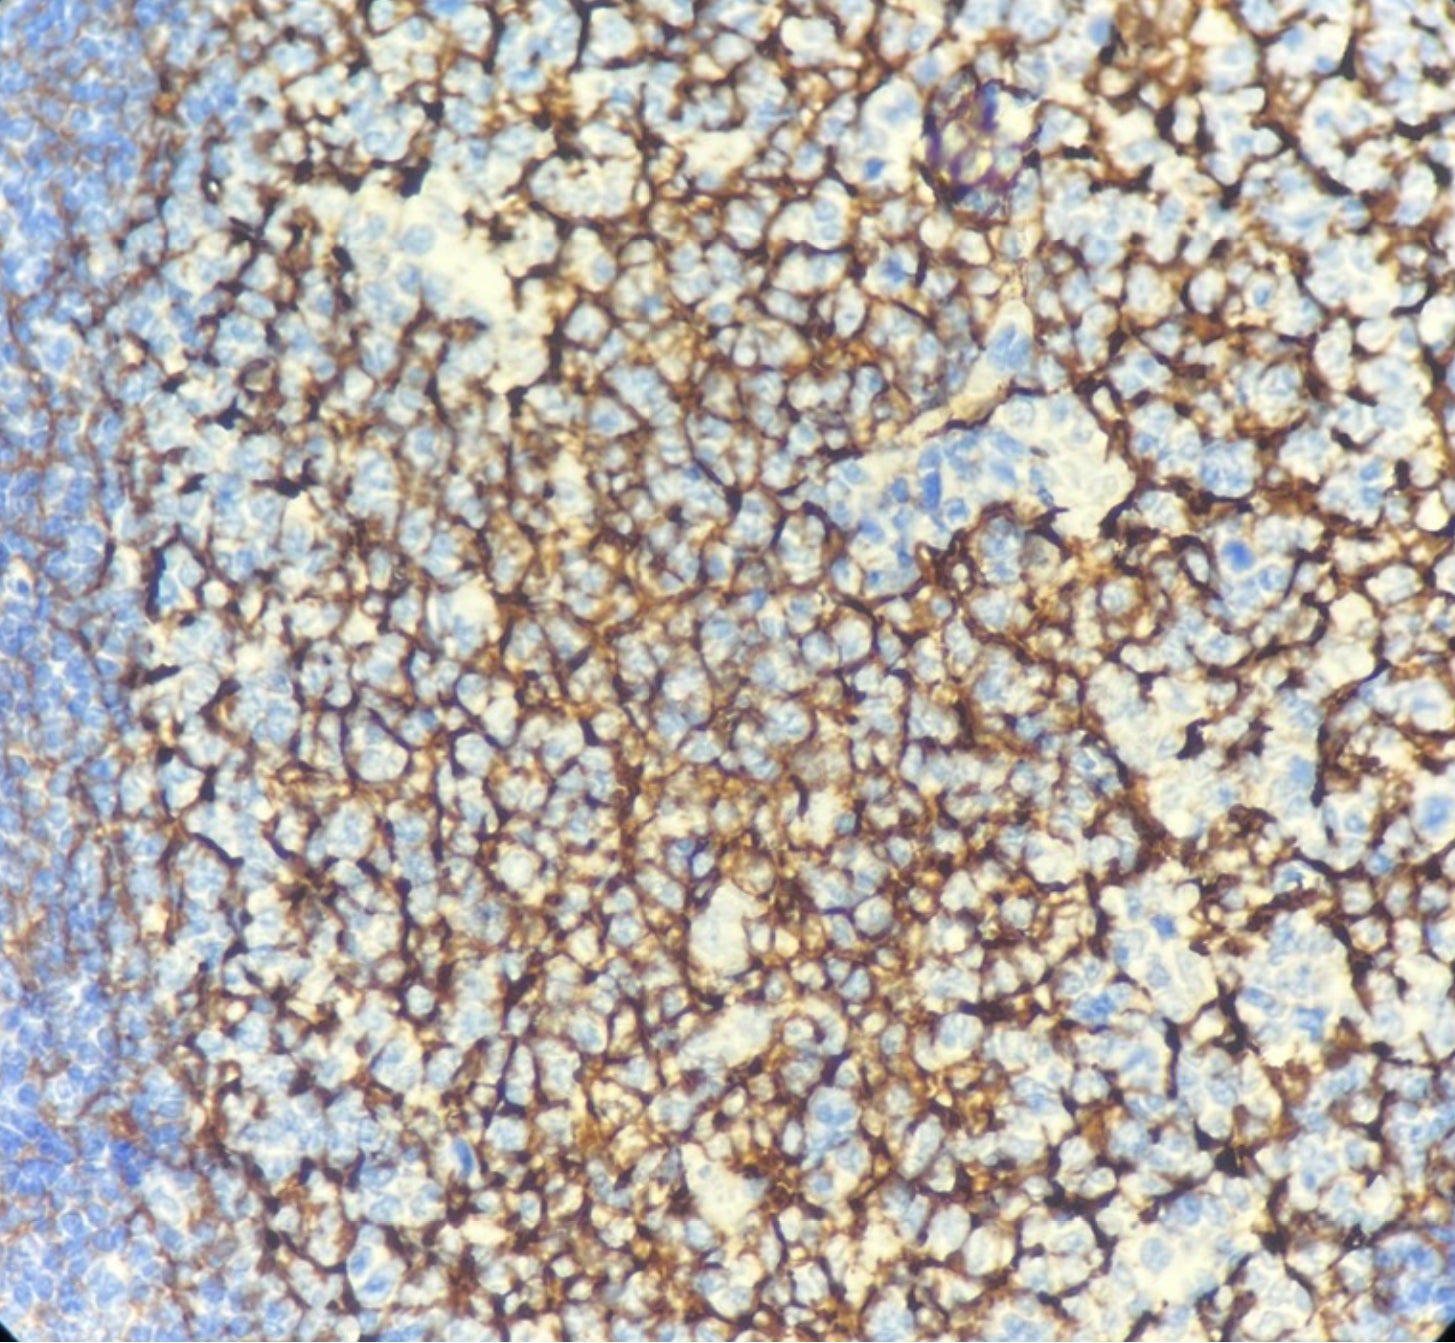

CD21, également connu sous le nom de CR2 (récepteur du complément 3d / récepteur 2 du virus Epstein-Barr), est une glycoprotéine membranaire intégrale de 140 kDa impliquée dans le fonctionnement du système du complément.

Il est spécifiquement exprimé sur les cellules dendritiques folliculaires des ganglions lymphatiques normaux et des amygdales, et n’est pas exprimé sur les lymphocytes T, les monocytes ou les granulocytes.

Cette protéine se lie au fragment C3d du complément. Son récepteur est exprimé à la surface des lymphocytes B, permettant au système du complément de réguler l’activation et la maturation des cellules B.

Le récepteur du complément de type 2 (CR2), en tant que protéine membranaire des lymphocytes B, sert également de récepteur d’entrée au virus Epstein-Barr lors de l’infection des cellules B et permet de marquer les tumeurs ou sarcomes des cellules dendritiques folliculaires.

Contrôle positif : Tissu amygdalien